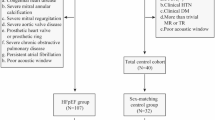

Non-invasive myocardial work (MW) by left ventricular (LV) pressure–strain loops (PSL) is a novel method for assessing myocardial function while adjusting for afterload, yet pediatric data remain lacking. The aims of this study were to investigate the different patterns of LV PSL and non-invasive MW in pediatric patients with hypertrophic (HCM) and dilated cardiomyopathy (DCM) and their association with exercise tolerance. We included 110 pediatric subjects (mean age, 13 ± 4 years, 35 DCM, 40 HCM, and 35 healthy controls). Standard and speckle-tracking echocardiography were performed. LV PSLs were generated, and global work index (GWI), MW efficiency (GWE), constructive work (GCW), and wasted work (GWW) were compared between groups. Regression analysis was used to assess the influence of ventricular function, dimensions, wall thickness, and wall stress on MW and to predict the association between MW and VO2 max as a surrogate of exercise capacity. Patients with DCM had significantly lower GWI compared to controls (GWI 479.6 ± 263.0 vs 1610.1 ± 211.0, P < 0.005). GWE was significantly reduced in DCM (79.3 ± 7.9 vs 95.2 ± 1.3, P < 0.005) due to significantly reduced GCW and increased GWW. HCM patients had significant reduction in GWI and GWE from normal (1237.7 ± 449.1 vs 1610.1 ± 211.0, P = 0.001 and 89.6 ± 4.9 vs 95.2 ± 1.3, P < 0.005, respectively), although less severe than with DCM. In a multivariate regression analysis, GWE had the highest association with VO2 max in both cohorts (DCM: β = 0.68, P = 0.001, HCM: β = 0.71, P = 0.007). Non-invasively assessed myocardial work and LV PSLs provide novel insights into the mechanisms of dysfunction in pediatric patients with cardiomyopathy with good prediction of clinical status and thus hold promise to further explore myocardial mechanistic with clinical relevance in different disease entities.